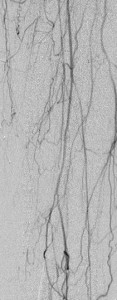

Key to images:

Top panel: Pre-intervention run-off angiogram of the left lower extremity showing, from left to right, irregular left common femoral artery (LCFA) arrowed on the 1st image, absent left superfical femoral artery (LSFA) or any bypass conduit on the 2nd image, sketchy descending collaterals from the left deep femoral (LDFA) that reconstitute a faint shadow of the left popliteal artery, arrowed on the 3rd image. The last 2 images faintly show three-vessel run-off below the left knee. The anterior tibial artery is most opacified, followed by the posterior tibial artery; the peroneal artery peeps through the upper edge of the last image. Note how weakly visible these vessels are due to the poor inflow from above.